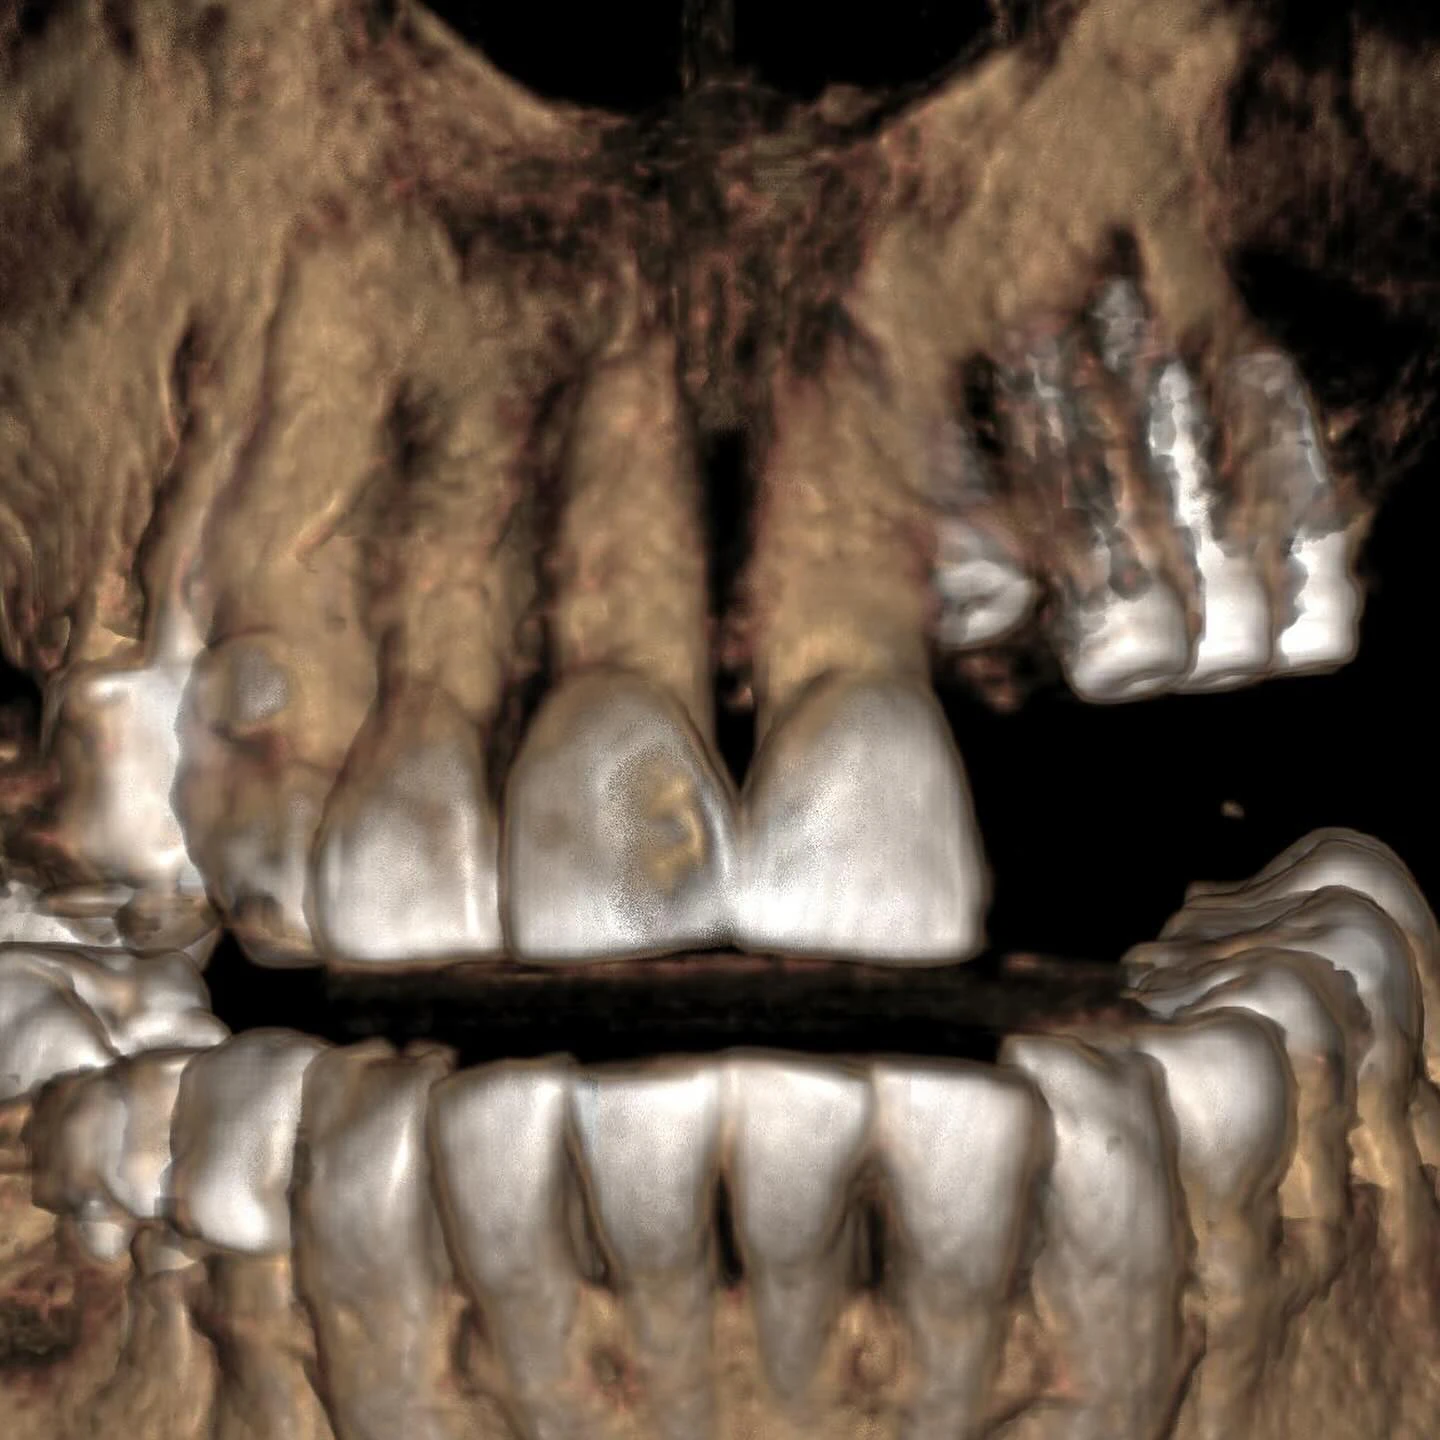

Każde leczenie w naszej klinice rozpoczynam od wnikliwej diagnostyki. W przypadkach, gdy podejrzewamy trudne warunki kostne w szczęce, absolutnym standardem jest u nas wykonanie tomografii wiązki stożkowej (CBCT). To badanie dało nam precyzyjny, trójwymiarowy obraz struktur anatomicznych pacjentki. Analiza skanów 3D potwierdziła nasze przypuszczenia: po utracie zębów doszło do znacznego zaniku wyrostka zębodołowego, a dno zatoki szczękowej – pustej przestrzeni w kości szczęki – obniżyło się tak bardzo, że ilość pozostałej kości była niewystarczająca do bezpiecznego wprowadzenia nawet najkrótszych implantów.

Zabieg polegał na delikatnym uniesieniu błony śluzowej zatoki i wprowadzeniu materiału kościozastępczego. Bezpośrednio po tym, w trakcie tej samej wizyty, w przygotowane miejsce wprowadziłam implanty dwufazowe. Kluczowym warunkiem powodzenia takiej zintegrowanej procedury jest uzyskanie tzw. stabilizacji pierwotnej implantu w kości własnej pacjentki.

Po okresie gojenia wykonaliśmy kontrolne badanie CBCT, które potwierdziło wspaniały rezultat regeneracji kości. Przyszedł czas na wszczepienie implantów dwufazowych. Są to tytanowe wszczepy, które po wprowadzeniu w kość zostają całkowicie zaszyte pod dziąsłem na okres osteointegracji, czyli zrastania się z kością. To klasyczna i niezwykle dobrze udokumentowana naukowo metoda, która w skomplikowanych przypadkach daje największą pewność sukcesu.